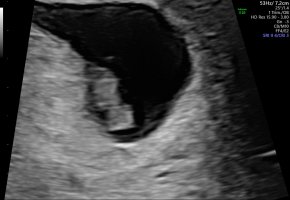

Er det noen som har vært på ultralyd rundt uke 7+6? Jeg har bestilt time til da og er så spent på hva vi får se! Gjerne sleng med bilde om dere har

Skikkelig fint bildeVis vedlegget 382557

Dette var vel 7+5, hode, rumpe, arm og fot ses her. Ikke mye en se så tidlig, men vi var for å se etter hjerteslag og det fikk vi se.